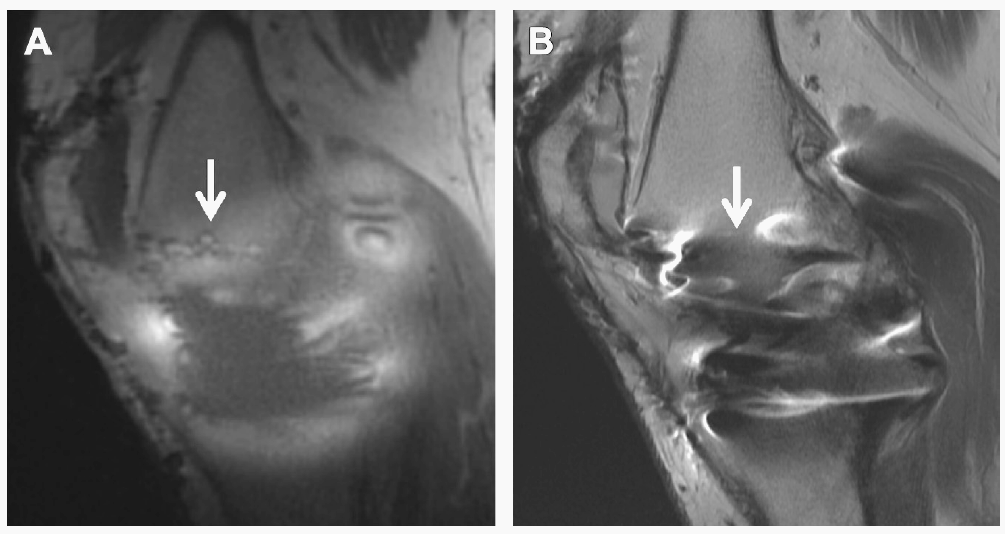

Improved periprosthetic visualization with UTE-MAVRIC compared with T1-weighted FSE. Patient status after medial unicompartmental knee arthroplasty several years previously using cobalt-chromium alloy components (A, B). Sagittal UTE-MAVRIC image (A) allows visualization of a pin tract used for the distal femoral cutting block (arrows), which was not evident on the conventional sequence (B).